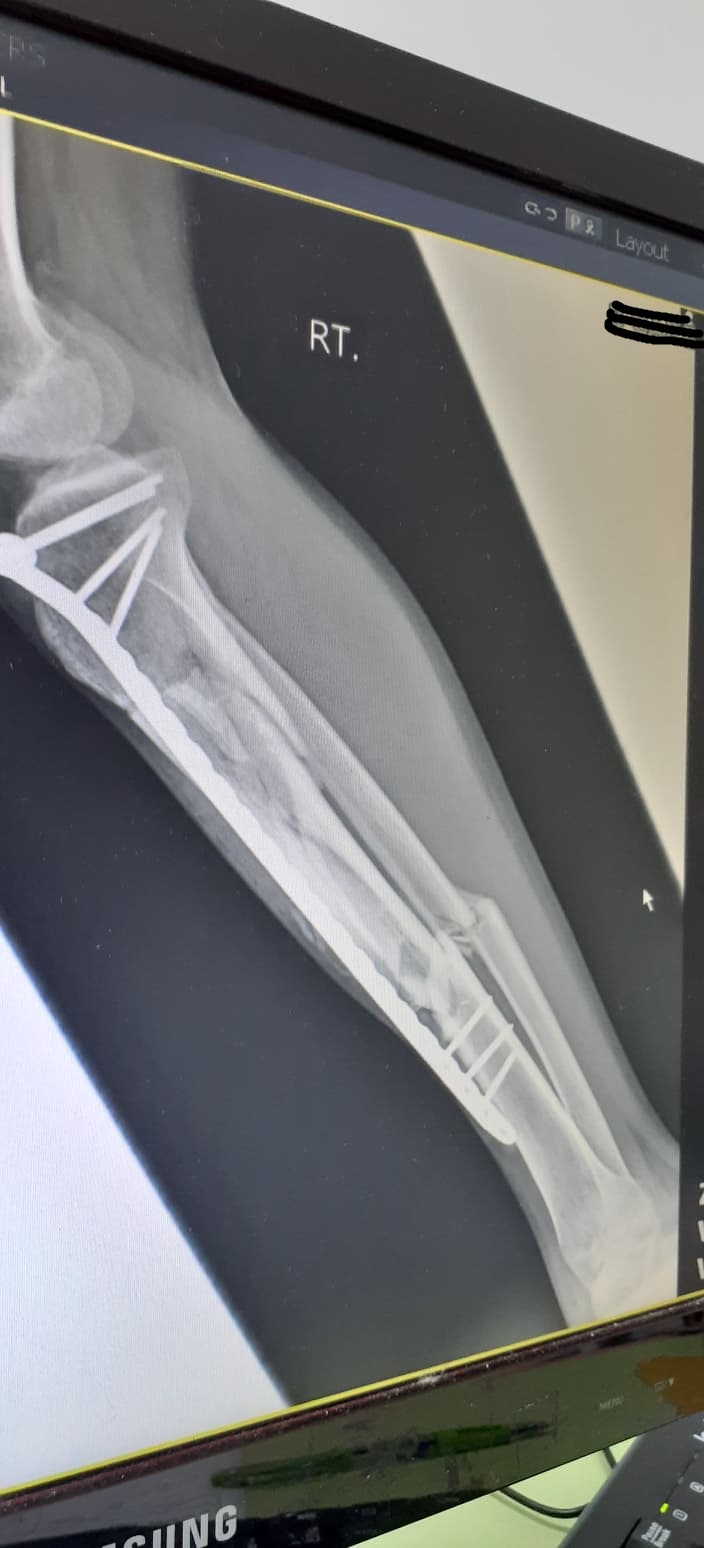

จากภาพเอกซเรย์ที่ปรากฏ หลังจากผ่าตัดมาแล้ว10เดือนครับ คุณหมอให้ลงน้ำหนักได้บ้างโดยการใช้ไม้ค้ำยันเป็นตัวช่วยพยุง แต่แกบอกว่าถ้ามีอาการเสียวให้หยุดเดิน1-2อาทิตย์ตรงนี้หมายความว่าผมสามารถเดินแบบลงน้ำหนักได้ตลอดใช่ไหมครับ (อาการเวลาเดินค่อนข้างจะเจ็บช่วงน่องขามาก)

ภาพข้างล่างหลังจากผ่าตัด4เดือน